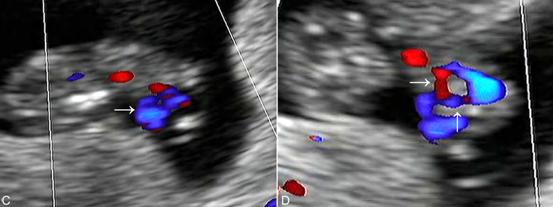

月经后第4周胎盘循环已建立,但经腹超声显像检查要在第7孕周以后、当妊娠囊其他部位的蜕膜反应形成的强回声变薄后才能在妊娠囊一侧显示局限性增厚及密集回声的胎盘。早期的胎盘面积多较大,可以占据子宫腔的1/2~1/3以上;第9孕周~10孕周以后可显示典型的胎盘回声,边缘清晰可认。正常胎盘显示为新月形、弥漫性均匀一致的中等强度回声。胎盘与胎体之间的脐带显示为绳索状回声,漂浮在羊水内。由于脐带较细,多数于早期妊娠过程中常规超声显像检查显示不清,彩色多普勒血流显像检查可以脐带的血流(图2,3)。

图2 早孕期脐带[C:11周胎儿脐带游离段血流(→);D:11周胎儿体内脐静脉(→)及脐动脉血流(↑